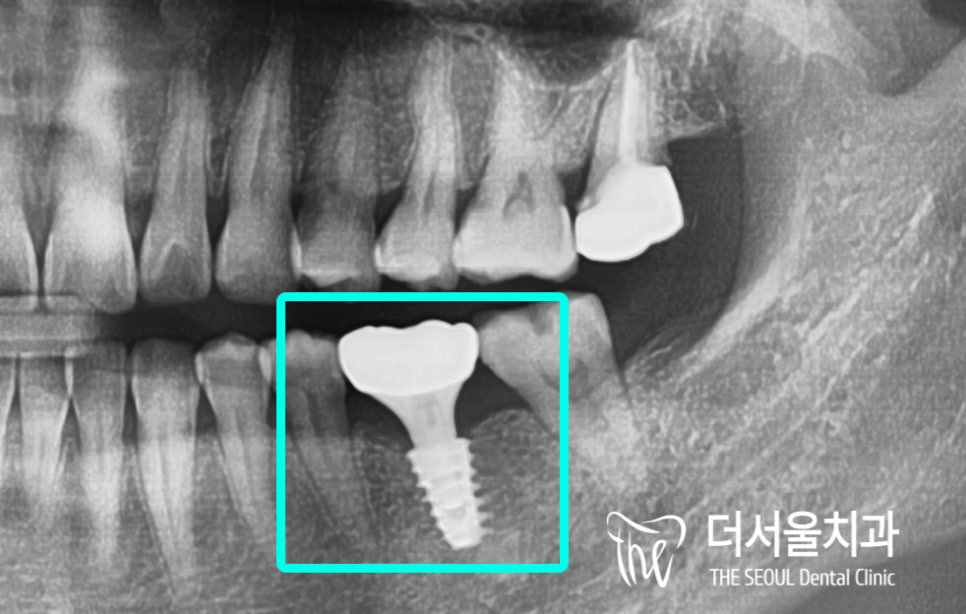

디지털 분석을 통해 식립될 위치와

픽스쳐의 종류, 직경들을 결정한 뒤

본격적인 최소절개임플란트 과정으로 들어갔는데요,

계산된 위치에 맞춰

최소절개임플란트 를 진행했습니다.

픽스쳐의 고정력 등을 확인하고

최종 보철을 올려드리기로 했는데요.

초기고정력도 좋은 편이였으머

무엇보다 알려드린 주의사항들을

너무나 잘 지켜주셨기 때문에

예상했던 것보다 좀 더 빨리

보철을 올려드릴 수 있었습니다.